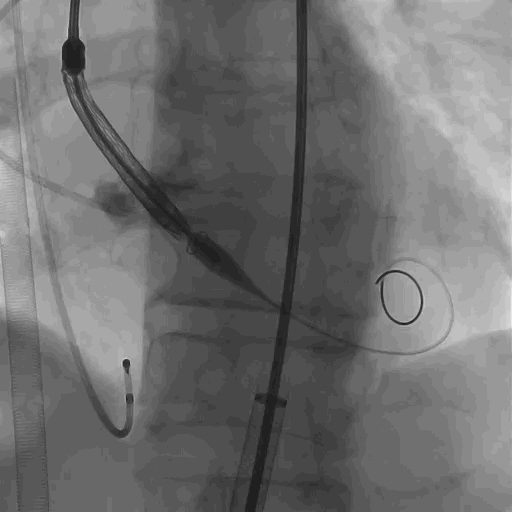

主动脉根部造影,有中大量反流。

主动脉根部造影

导丝跨瓣,多次跳出,跨瓣困难。

导丝跨瓣

球囊预扩,考虑心室大,心衰的征象存在,术前ECMO辅助患者进行循环,预扩时反流量将球囊上冲,等患者恢复后进行第二次扩张,球囊无腰无漏,冠脉显影明显。

球囊预扩